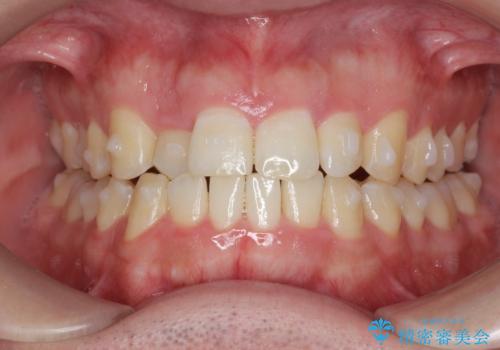

前歯が隠れていて見えない クロスバイトの矯正治療

- 「前歯が1本隠れていて見えない、歯並びを矯正治療で改善したい。」と希望され来院されました。

前歯のスペース不足により1本だけ後方に位置している状態でしたが、しっかりとスペースを確保し配列することができました。